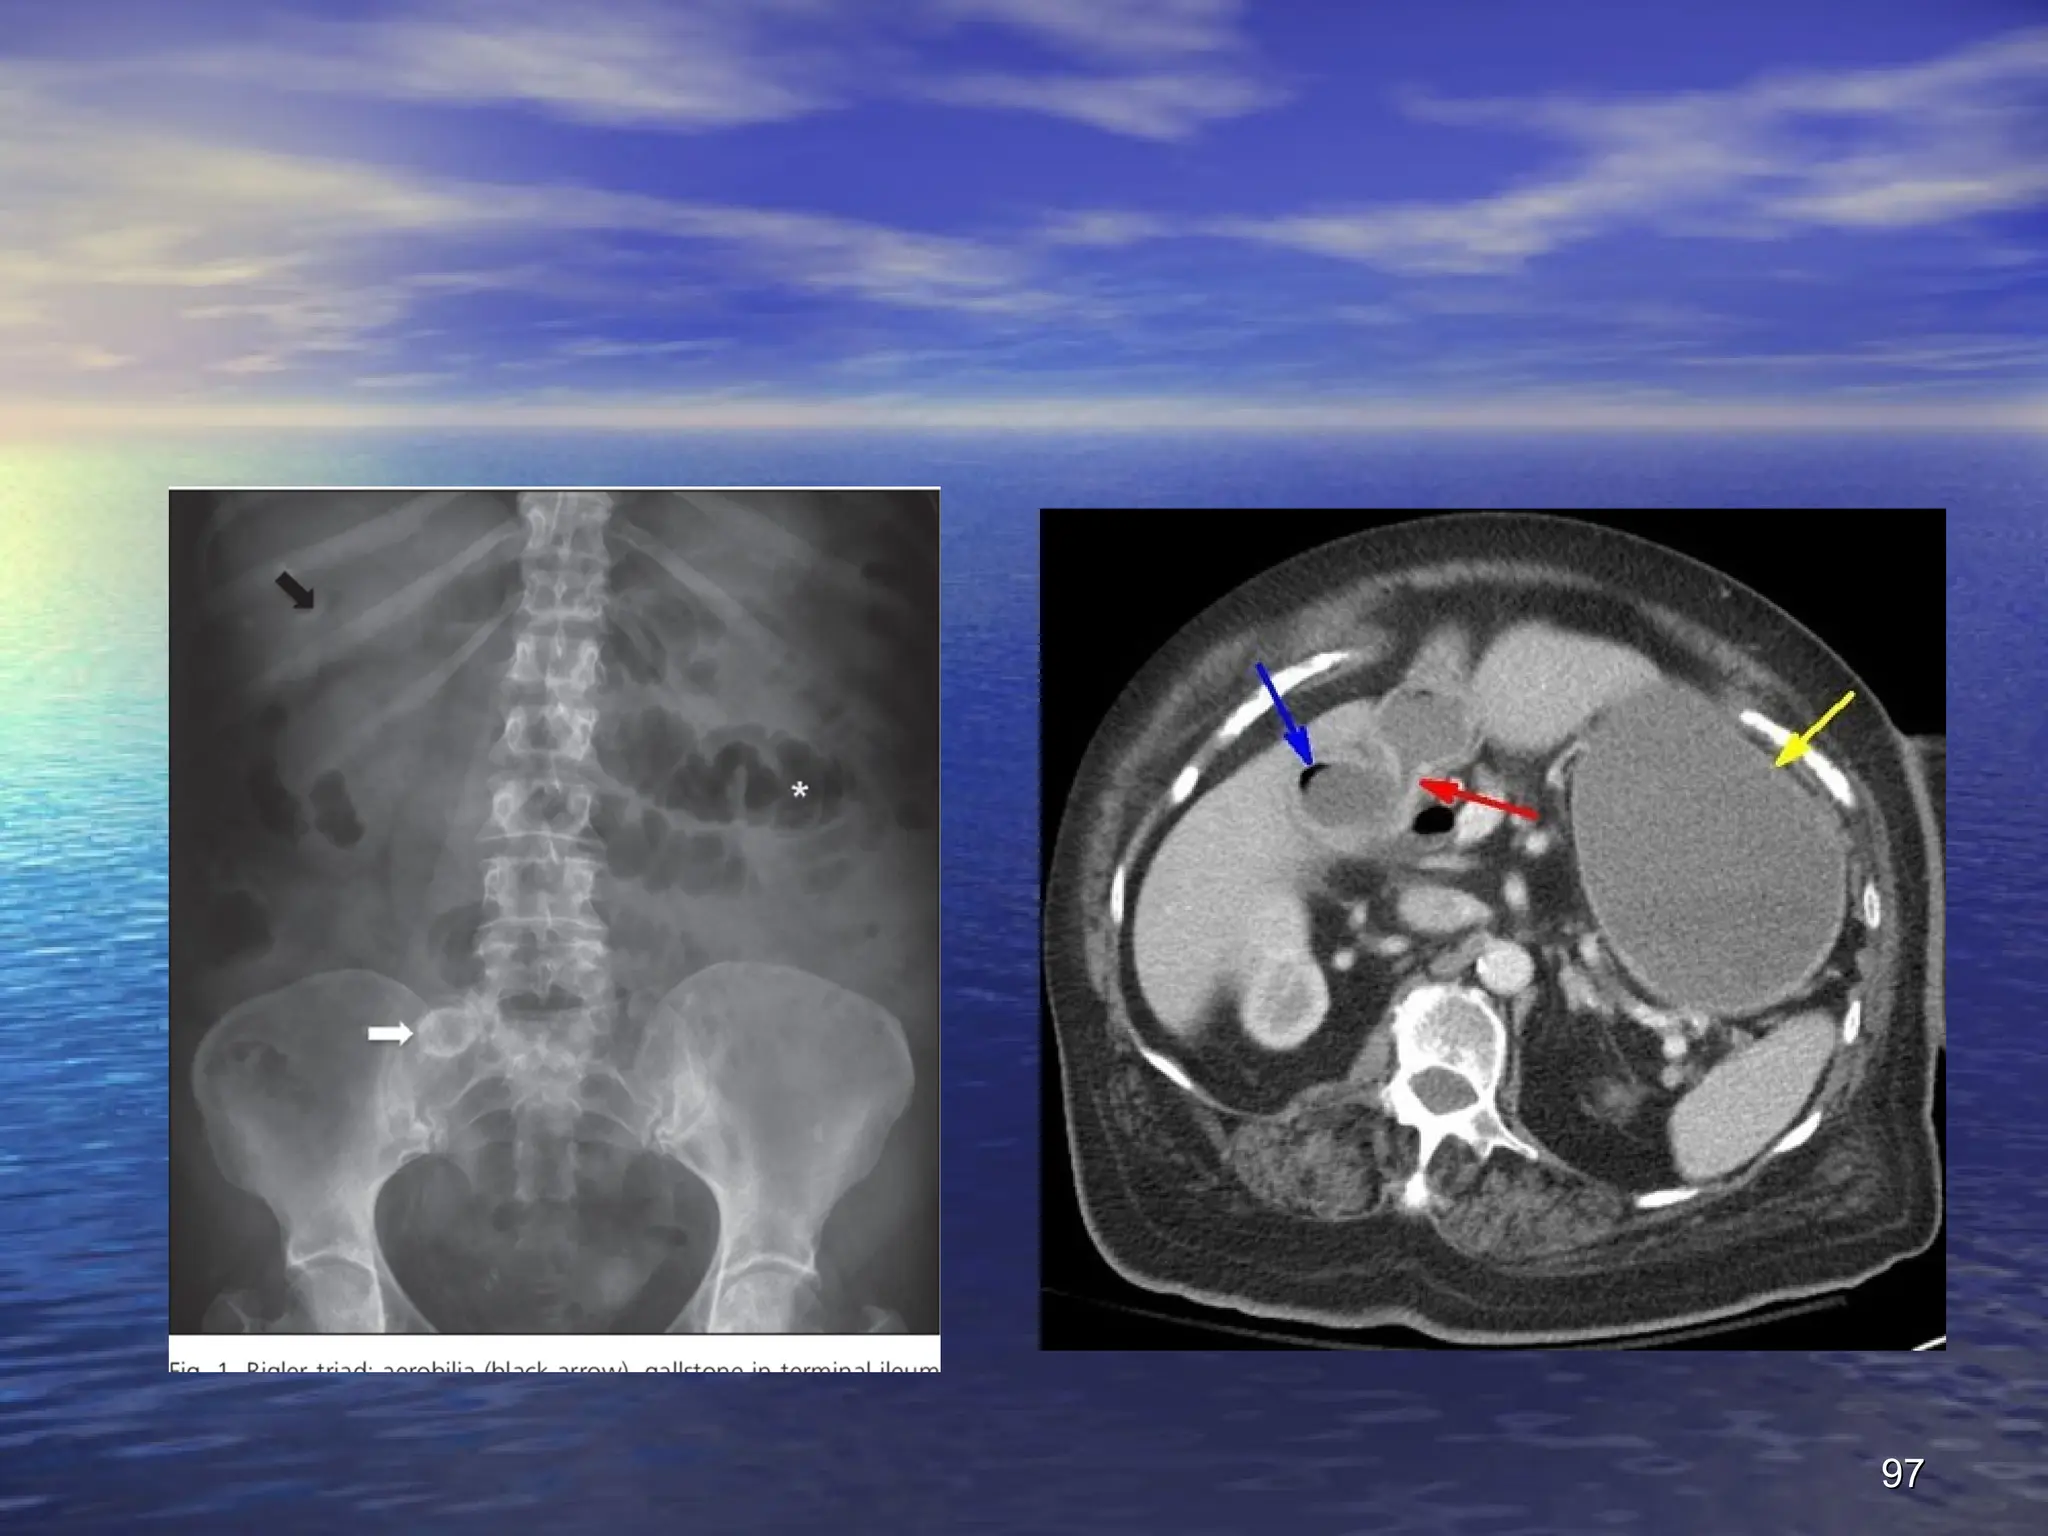

Radiography

- :

The characteristic radiological sign of gallstone ileus

is

Rigler's triad

:

small bowel obstruction

small bowel obstruction +

+ pneumobilia

pneumobilia +

+ atypical

atypical

mineral shadow on radiograp ectopic calcified

gallstone, usually in the right iliac fossa

Presence of two of these radiological signs has been

considered pathognomic of gallstone ileus

.